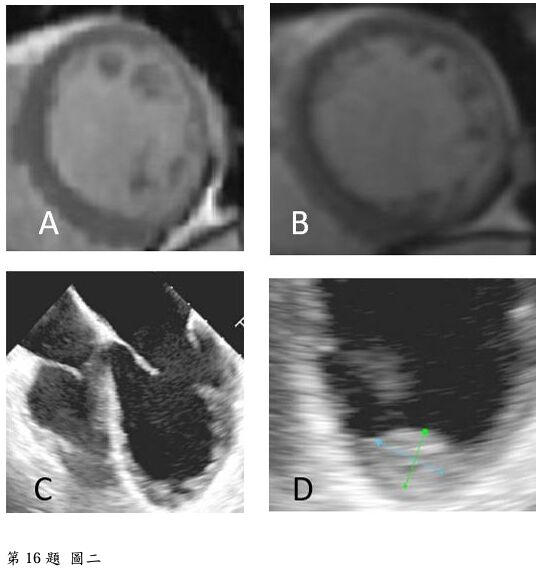

16. 一位55歲女性病患因端坐呼吸與動喘一週而來住院。身體診察發現血壓90/56毫米汞柱,心跳每分 鐘102下,頸靜脈怒張,心音低遠併第三心音,肺部有囉音,雙下肢小腿與腳部水腫。心電圖如圖一。心臟超音波呈現左心室擴大,瀰漫性左心室收縮功能異常,左心室射出分率(left ventricle ejection fraction)為25%。心臟磁振造影檢查如圖二A與B。經食道心臟超音波如圖二C與D。請問下列敘述何者錯誤?

(1)該病患的心電圖呈現 low voltage in frontal leads (2)該病患心電圖呈現心房顫動 (3)該病患之心臟磁 振造影影像檢查呈現左心室心肌緻密化不全(left ventricular non-compaction) (4)該病患之心臟磁振造影影 像檢查呈現急性心肌發炎 (5)該病患應使用口服抗凝血劑 (6)這種疾病有時是因肌節(sarcomere)基因異常 引起 (A) (1)+(3)+(6)。 (B) (2)+(3)+(5)。 (C) (2)+(4)。 (D) (2)+(4)+(5)。